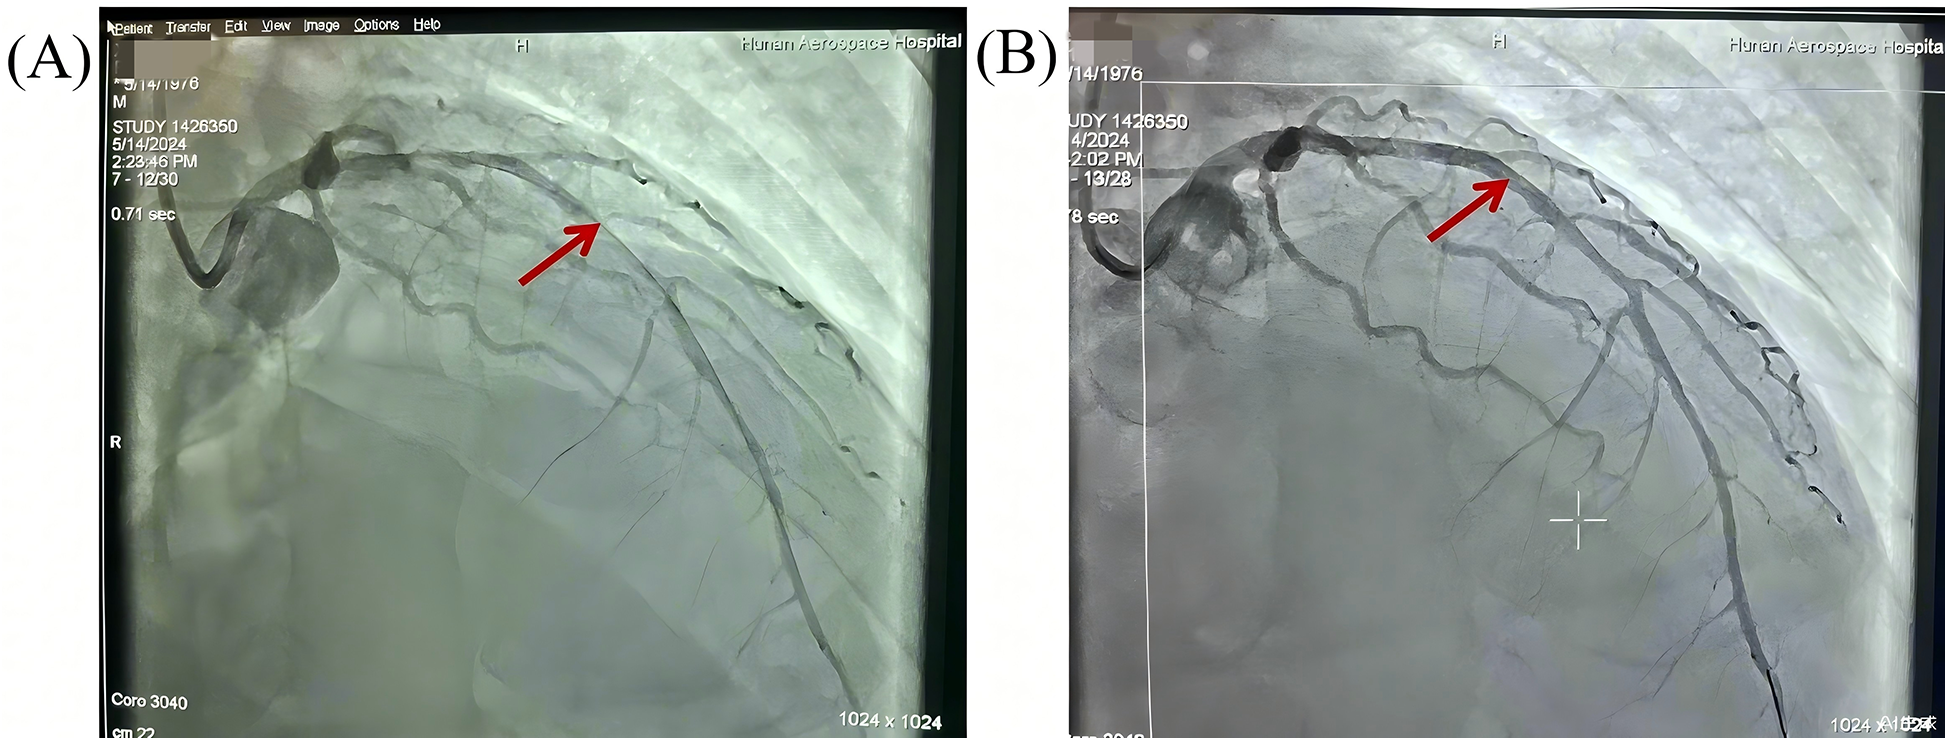

Given the suspicion of acute myocardial infarction, the patient was emergently transferred to our tertiary cardiac center for definitive revascularization under ongoing ECMO support. He arrived in our catheterization laboratory at 1:50 PM. Coronary angiography revealed multivessel coronary artery disease, especailly diffuse tubular stenosis in the proximal-to-mid left anterior descending (LAD) artery, causing 50%–90% luminal narrowing (Figure 1). A drug-eluting stent was implanted to restore coronary perfusion, with a “door-to-balloon” time of 18 min.

Figure 1

Pre- and post-PCI angiographic evaluation of diffuse stenosis in the left anterior descending artery. (A) Pre-PCI angiography: Diffuse tubular stenosis involving the proximal-to-mid LAD (arrows) with 50%–90% luminal narrowing. (B) Post-PCI angiography: a drug-eluting stent deployed across the lesion, achieving normalized antegrade flow (TIMI-3 flow).